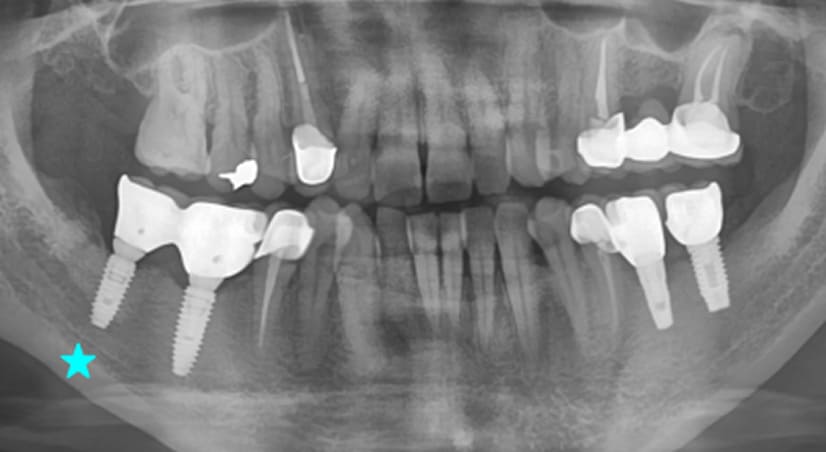

13+ 年

-

种植体植入:2012 年 9 月 -

最终修复体:2013 年 1 月 -

随访:13 年(2025 年 1 月)

种植体植入 2012年10月 -

最终修复体 2013年1月 -

随访:13年 2025年3月

9年以上

随访:2年 2014年7月 -

随访:9年 2021年9月